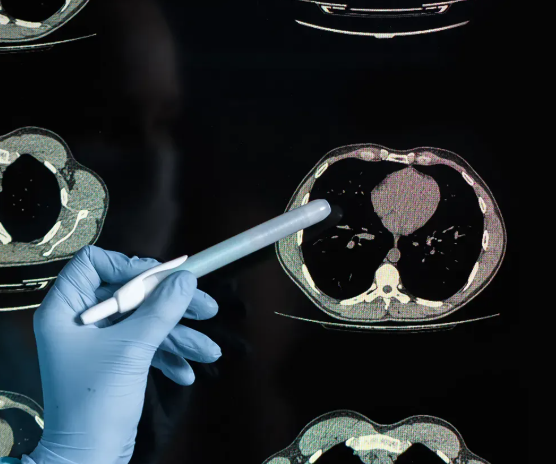

CT 결과지를 읽을 때 알아두면 좋은 포인트

CT 판독지는 영상의학과 전문의가 작성하며, 여러 전문 용어가 포함되어 있습니다. “결절(nodule)”, “침윤(infiltration)”, “음영(opacity)” 같은 단어가 자주 등장합니다. 처음 보는 사람에게는 어렵게 느껴지지만, 기본 개념을 알고 읽으면 대략적인 상황을 이해할 수 있습니다.

결절은 작은 혹을 의미하며, 대부분 양성이지만 크기와 형태에 따라 추적 검사가 필요할 수 있습니다. 침윤은 염증이나 감염이 의심되는 상태를 뜻하고, 음영은 비정상적인 조직 밀도를 표현하는 용어입니다. 결국 단어 하나보다는 이전 검사와 비교해 변화가 있는지가 핵심입니다.

예를 들어 작년에 찍은 CT에서는 깨끗했는데 올해 영상에서 새로운 음영이 생겼다면, 그 원인을 파악하는 것이 중요합니다. 이때 같은 병원, 같은 장비에서 정기적으로 촬영하면 변화 추적이 훨씬 용이합니다. 따라서 장기적인 건강 모니터링을 위해서는 정기적인 동일 조건 촬영이 바람직합니다.